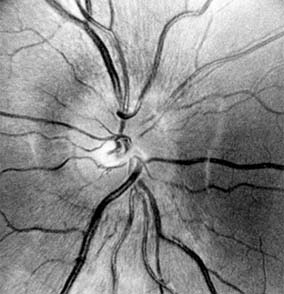

Figure 14-8

Figure 14-8: Mild disk swelling in demyelinative papillitis, with disk leakage on fluorescein angiography.